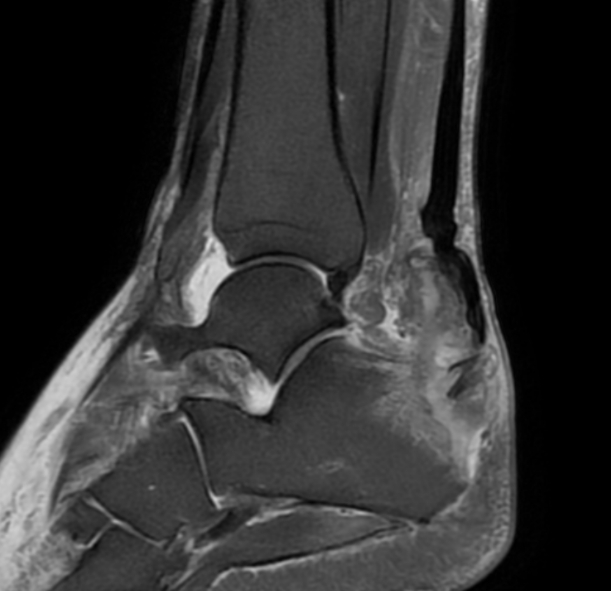

足踝骨科主任王春玲接诊了马先生,为其仔细查体后发现,他左足跟腱走行区可触及空虚感,左踝关节跖屈活动受限,考虑为跟腱止点断裂。随后的磁共振检查验证了这一诊断,马先生被诊断为左足跟腱断裂、跟腱止点撕脱性骨折。

术前MRI